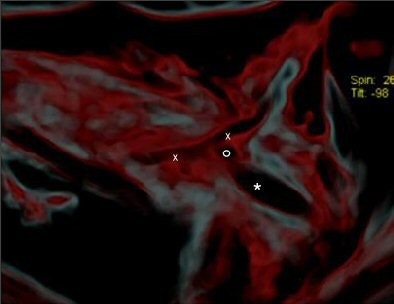

![]() |

| CT image shows the injury (x-x) and the head of the arrow (*). Figure published in: JArcheol Sci, in press, Pernter P., Gostner P., Egarter Vigl E., Rühli, F. J., "Radiologic proof for the Iceman's cause of death (ca 5300 BP), Copyright Elsevier. Image courtesy of Dr. Frank Rühli and the University of Zurich, Switzerland. |

Using MDCT, the researchers were able to identify the subclavian artery with its higher density (-40 HU), compared to the surrounding soft tissue (-290 HU), and found damage to the left dorsal artery wall that was 13 mm in length. Also visible was a 3-mm irregular pseudoaneurysm, which they noted was a typical complication of a subclavian artery laceration. A large hematoma was seen in the surrounding soft tissue, and the arrowhead (+1840 HU) was found in situ 6.5 mm away in the dorsocranial direction, they added.

"It seems most likely that (the arrowhead) lacerated the subclavian artery. By removing the shaft of the arrow perimortem, its head must have been slightly retracted to the actual position where the barbs caught in the tissue and, eventually, the arrowhead separated from the now missing shaft," the group wrote. "In the surrounding soft tissue one can see linear air incorporations as well as multiple irregular partially confluent densities (-80 HU), with the latter likely representing a hematoma. It spreads dorsocaudally between the ribs and the scapula, and also into the shooting channel toward the subcutaneous soft tissues" (Journal of Archaeological Science, March 15, 2007).